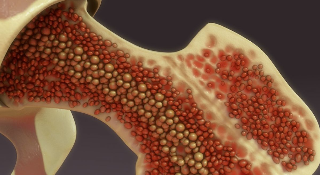

Разработан новый метод лечения синдрома недостаточности костного мозга

В новости сообщается о разработке нового метода лечения синдрома недостаточности костного мозга...